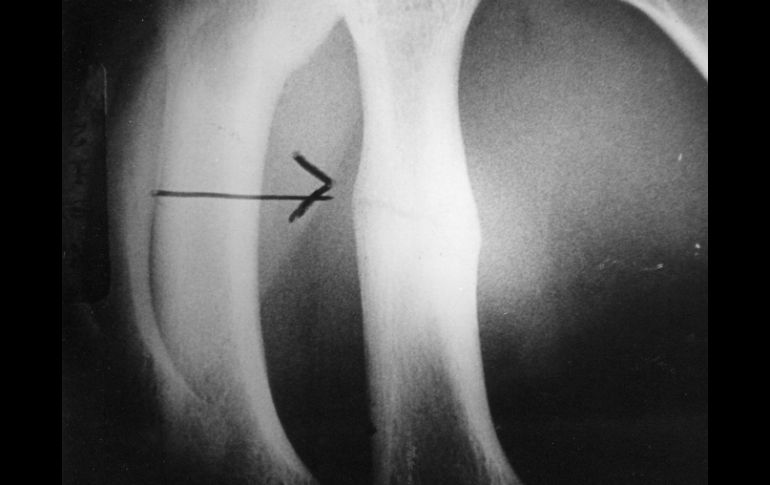

El especialista manifestó que la osteoporosis, "como su nombre lo indica, se caracteriza por la porosidad ósea que torna los huesos frágiles y por lo mismo más susceptibles a quebrarse".

Añadió que la evidencia más clara de su presencia es una fractura, siendo las de cadera las más frecuentes, aunque también se puede producir en la columna, con una tasa de mortalidad a dos años de 50 y 23 por ciento, respectivamente.